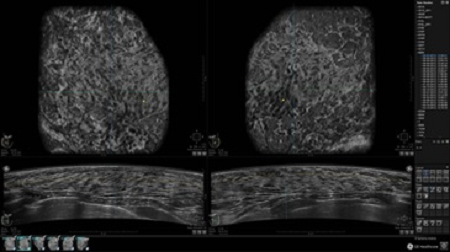

• Многооконный просмотр: 4 - 12 изображений

• Оптимизированные протоколы обзора для большого потока пациентов

• Стандартизованная ориентация изображения: «толстый срез» в коронарной плоскости; поперечная; сагиттальная плоскость; радиальный и антирадиальный поворот изображения; просмотр исключительно области интереса

• Изменяемая толщина среза: 0,5 - 10,0 мм (шаг 0,5 мм)

• Срез: 0,5 - 2,0 мм (шаг 0,5 мм)

• Одновременный просмотр двух изображений для сопоставления в коронарной плоскости